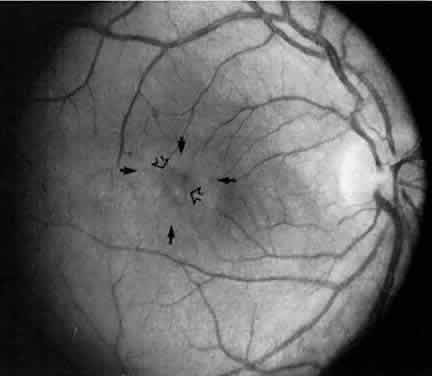

Retinal changes that can occur in pars planitis include perivascular sheathing of the retinal venules (periphlebitis), cystoid macular edema, and optic disc edema (Figs. 3 and 4). In cases of chronic cystoid macular edema, epiretinal membrane formation often occurs.4,13,27

Fig. 3. Pars planitis. Cystoid macular edema. Black arrows point to a halo of edema surrounding the macula. Open arrows point to cysts in the macula.